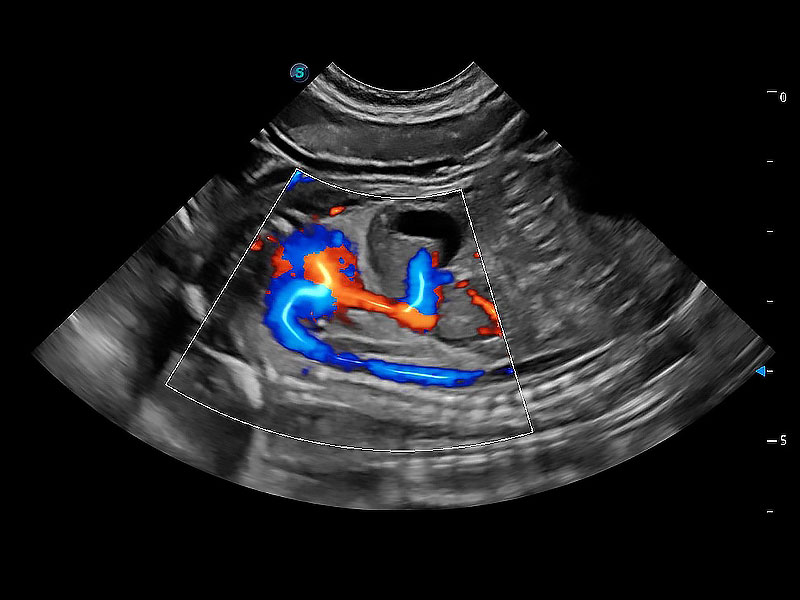

得心應(yīng)手 心臟解決方案

ProPet 80 配備了豐富的心臟探頭群、先進(jìn)的成像技術(shù)和專業(yè)的心臟測量工具,可幫助動物醫(yī)生為不同體型和生理結(jié)構(gòu)的動物提供心臟和心肌功能的全面評估。

(犬)二腔心血流

(犬)胎兒主動脈弓立體血流